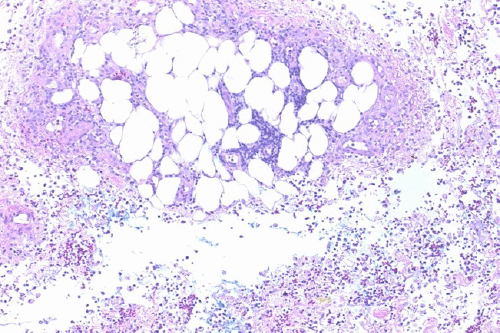

Upper endoscopy with endoscopic ultrasound was performed to evaluate for malignancy—no pancreatic mass was identified. Given the draining nodules on physical exam were suggestive of fat necrosis and an extensive rheumatologic workup of the patient's polyarthritis was negative, a skin biopsy of the left wrist nodule was performed. This demonstrated dense dermal and subcutaneous necrotizing neutrophilic inflammation consistent with pancreatic panniculitis (Figure 5).1 Wound culture from the nodules was negative for pathogenic organisms.

Figure 5. Representative Histopathological Images at (A) 20x, (B) 100x, and (C) 200x Magnification of Left Wrist Punch Biopsy. Published with Permission

A.

B.

C.

Images demonstrate diffuse dermal and subcutaneous necrotizing neutrophilic inflammation.